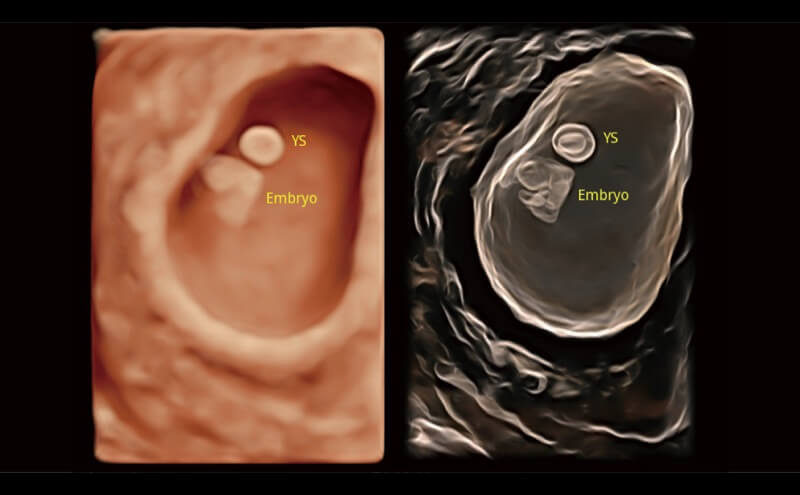

Ultraschall wird immer vielseitiger und übernimmt immer mehr klinische Aufgaben. Als Vorreiter, der Ärzten dabei hilft, mehr zu erreichen, ist ELITE mit einer umfassenden Palette fortschrittlicher Funktionen für die Allgemeine Bildgebung, Gynäkologie/Geburtshilfe, Kardiologie und mehr integriert.

Ultraschall wird immer vielseitiger und übernimmt immer mehr klinische Aufgaben. Als Vorreiter hilft ELITE den Ärzten dabei, mehr zu erreichen, indem es mit einer umfassenden Palette fortschrittlicher Funktionen ausgestattet ist, die die allgemeine Bildgebung, die Geburtshilfe/Gynäkologie, die Kardiologie und vieles mehr abdecken.